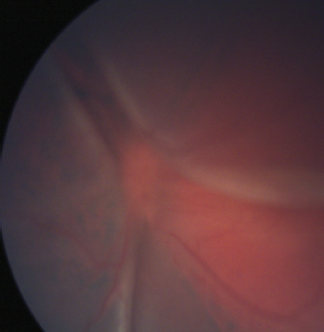

Six months later, the child developed photophobia and a granulomatous anterior chamber reaction in her other eye. Dilated fundus examination revealed Dalen-Fuchs nodules suspicious for sympathetic ophthalmia (Figure 5).

Figure 5. Color anterior segment photograph demonstrates granulomatous anterior chamber reaction, and fundus photograph shows Dalen-Fuchs nodules.

Courtesy of Ta Chen Peter Chang, MD